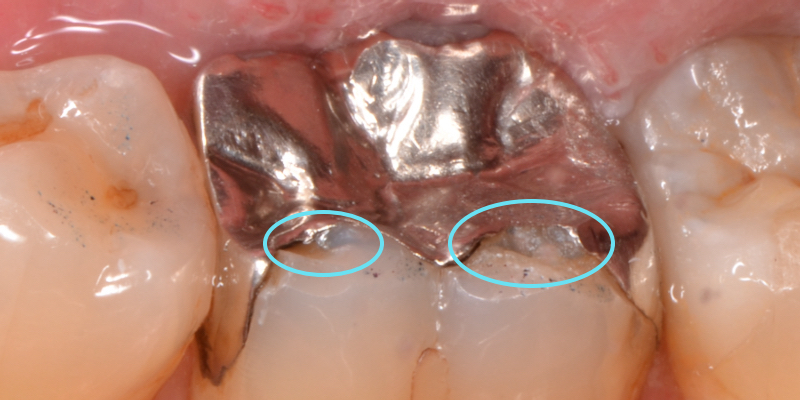

銀歯と歯の境目には、

- 左◯:歯が欠けた結果できた隙間

- 右○:咬み合わせの歯と強く当たって細かく欠けた跡

があります。

患者様は、「舌で触るとザラザラする」という感覚だと思います。

銀歯の下は

銀歯の下は、むし歯で黒くなっていました。